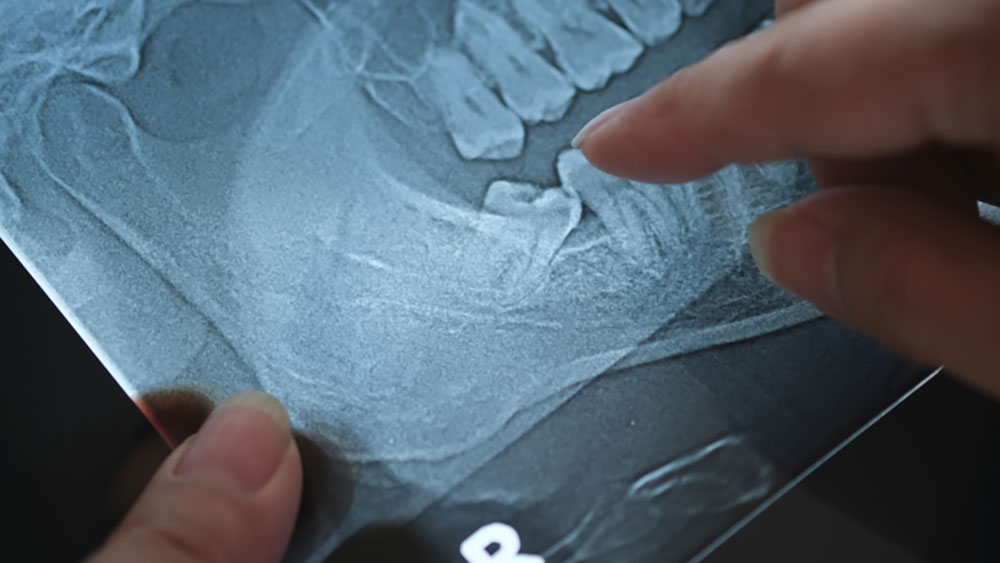

下顎の親知らずの生え方がよくない場合、一部見えているだけということもあれば、極端な例では上下逆さまになっている親知らずも見られます。

一見すると真っ直ぐに生えているように見えても、後ろ側が歯肉で覆われているということもあります。

横向きの場合でも、横に向く角度が外に大きく傾いている親知らずもあり、その場合の抜歯は親知らずの向きが歯並びに並行な場合以上に難しくなります。

小指より小さいこともあれば、親指くらいある親知らずもありますし、根が八の字のように広がっている親知らずもあれば、根は1本だけですらっとした親知らずもあります。

根の先がL字に曲がっていることもあり、歯の形の差がとても大きいのです。

もし、根の先が八の字に広がっていたり、L字になっていたりしたら、それだけで抜歯の難度がグッと上がります。